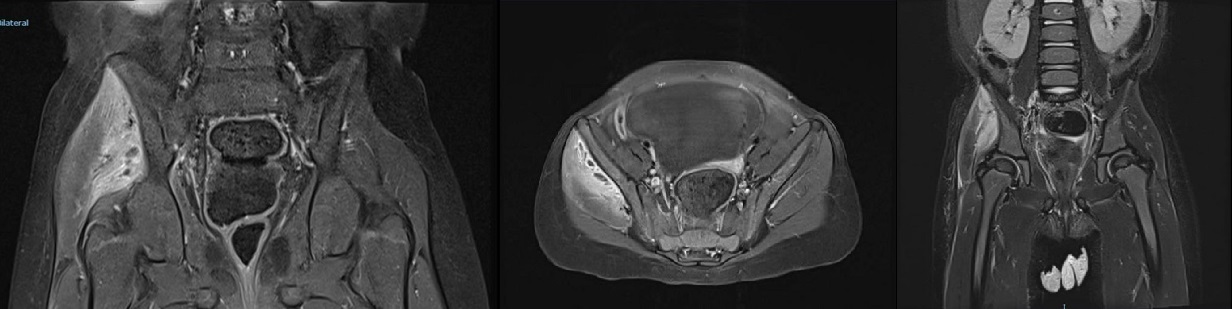

Ante la sospecha de infección osteoarticular, se inicia tratamiento antibiótico empírico precoz con cefuroxima intravenosa a 150 mg/kg/día, y se completa estudio con resonancia magnética de cadera, en la que se observa “hiperintensidad difusa del músculo glúteo menor y medio derechos, asociando microabscesos en dicha localización”; imágenes compatibles con piomiositis (Fig. 1).

Figura 1. Ilustración SEQ Ilustración\* ARABIC 1. Imágenes de resonancia magnética que muestran hiperintensidad a nivel de glúteo menor y medio derechos, con captación de contraste en la zona y pequeñas colecciones compatibles con abscesos intramusculares.